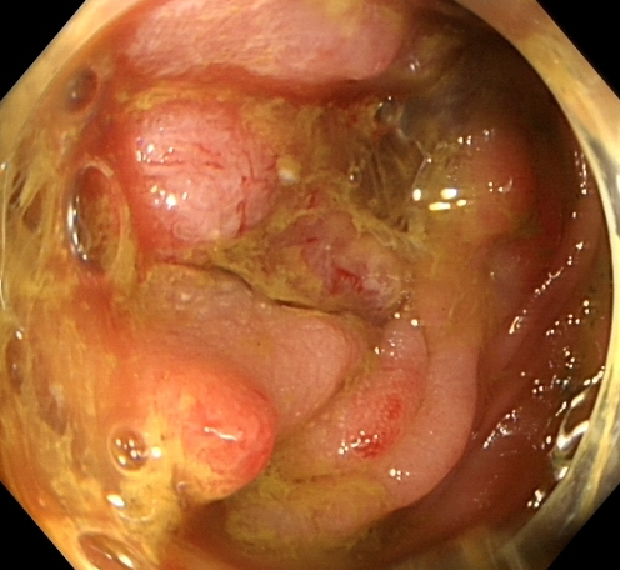

2020-02-04行肠镜检查示:进镜至距肛门30cm见一环腔生长的新生物,表面覆污苔,肠腔狭窄,内镜无法通过,活检质脆,易出血,另直肠见一大小约0.5x0.6cm的扁平息肉,表面光滑,余未见明显异常。

影像结论:结肠癌,直肠息肉。